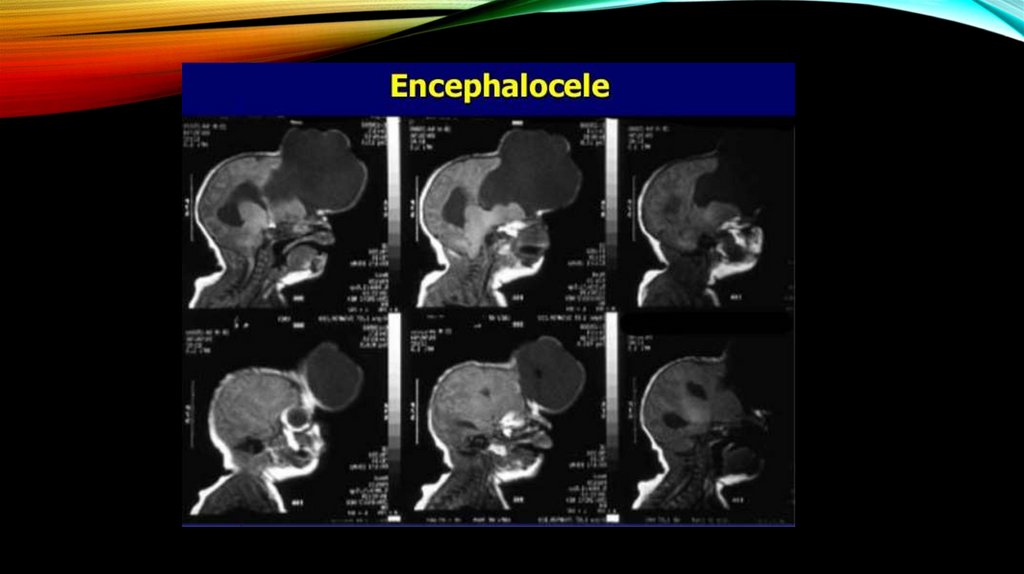

Phylogenetic Disorder of Neocortex

Phylogenetic disorders of brain

Phylogenitic disorders of CNS